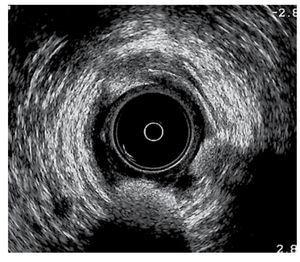

Caso 1. Hombre de 34 años de edad con antecedente de hemorroidectomía tipo Ferguson seis meses previos a su padecimiento, que inició con incontinencia a gases y materia fecal líquida con una frecuencia de tres veces al día. Asimismo, refería escurrimiento de materia fecal líquida de predominio nocturno. Recibió tratamiento con laxantes de volumen y loperamida (2 mg, tres veces al día) durante dos meses, sin mejoría de su sintomatología. Se le realizó un ultrasonido endoanal de 360o, en donde se observó una lesión anterior del esfínter interno (Figura 1). En la manometría se informó hipotonía de esfínter anal con presión en reposo de 70 mmHg y en contracción de 100 mmHg. La incontinencia fecal fue medida por medio de la escala validada de continencia de Jorge-Wexner (JW).3 En este paciente, su escala de continencia fue de 17 antes de la cirugía.

¿ Figura 1. Lesión anterior del esfínter anal interno.